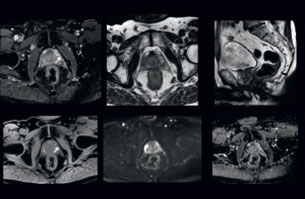

Visualizing critical structures with MRI before prostate radiation therapy

A 63-year-old patient with prostate cancer, cT3bNxM, Gleason 7, underwent MRI on Ingenia 3.0T MR-RT before radiation therapy.

Intraprostatic lesions are visible on the bTFE MR image, but not on the CT image. MRI shows excellent soft-tissue contrast for the visualization of critical structures like the rectum and penile bulb.

Fiducial markers (green arrows) are used in registration of MR images to CT, to transfer the MR-based delineations onto the CT image dataset.